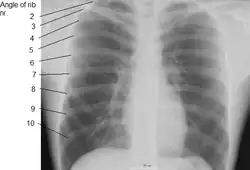

The angle of a rib (costal angle) may both refer to the bending part of it, and a prominent line in this area, a little in front of the tubercle. This line is directed downward and laterally; this gives attachment to a tendon of the iliocostalis muscle. At this point, the rib is bent in two directions, and at the same time twisted on its long axis.

The distance between the angle and the tubercle is progressively greater from the second to the tenth ribs. The area between the angle and the tubercle is rounded, rough, and irregular, and serves for the attachment of the longissimus dorsi muscle.

X-ray image of a human chest, with ribs labelled -